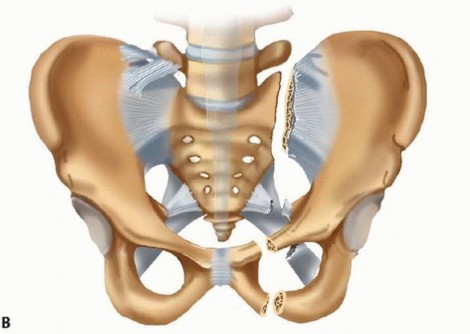

Applied forces can be simplified into anteroposterior (AP) compression, lateral compression, and vertical shear. Actual forces and accordingly mechanism of injury are likely more complex. Resultant instability patterns are categorized as (1) vertically and rotationally stable, (2) rotationally unstable and vertically stable, and (3) rotationally and vertically unstable. AP compression and hemipelvic rotational forces tend to result in injury to the “anterior ligamentous” complex (severity order: symphysis pubis, ischiosacral ligaments, anterior sacroiliac ligament). The integrity of the posterior tension band is preserved and vertical stability accordingly maintained ( FIG 1A). Depending on the severity of injury to the anterior ligamentous complex, rotational instability may ensue. Lateral compression injuries, depending on severity, may result in internal collapse of the pelvis. Ligaments both anteriorly and posteriorly generally remain intact. Osseous injuries both anteriorly and posteriorly are typically stable impaction variants. Occasionally, internal rotatory instability is sufficient to warrant surgical stabilization (external or internal fixation). Vertical instability implies disruption of the posterior tension band of the pelvic ring. This may be of osseous, ligamentous, or combined origin. Division of the sacrospinous and sacrotuberous ligaments in the presence of intact posterior ligaments will render a pelvis rotationally unstable. Further division of the posterior ligaments of the sacroiliac complex will result in both rotational and vertical instability. The involved hemipelvis is unstable in the axial, sagittal, and coronal planes ( FIG 1B). Any injury mechanism (AP compression, lateral compression, vertical shear) may result in complete (vertical and rotational) instability if the magnitude of force is sufficient. ## NATURAL HISTORY Life-threatening hemorrhage associated with pelvic fractures may be intrapelvic or extrapelvic. Identifying the source of bleeding may be challenging. 27 In the absence of extrapelvic and intraperitoneal sources, external fixation of the pelvis may prevent life-threatening exsanguination. Early sheeting (circumferential external compression) may offer an initial beneficial hemodynamic response. Suspected sustained hemorrhage of indeterminate source may be intrapelvic arterial in origin. 2 This may respond favorably to angiographic transcatheter embolization. Exploratory laparotomy, from the standpoints of role and timing, remains controversial. Imaging findings, results of diagnostic peritoneal lavage (if indicated), and response to fluid resuscitation must be considered before exposing the unstable trauma victim to the potential negative effects of abdominal exploration (decompression of intrapelvic tamponade, among others). 310

### FIG 1 • A. An external rotation injury (AP compression) resulting in “anterior ligamentous complex injury.” Instability is rotational in character and demonstrated in the axial plane. The posterior tension band is intact and vertical stability is preserved. B. A vertical shear injury. In addition to compromise to the “anterior ligamentous complex,” the integrity of the posterior tension band is disrupted. The involved hemipelvis is unstable in all planes. (Modified from Buckle R, Browner B, Morandi M. Emergency reduction for pelvic ring disruptions and control of associated hemorrhage using the pelvic stabilizer. Tech Orthop 1995;9:258-266.) Pelvic fractures associated with violation of the perineal, rectal, or vaginal regions must be identified immediately, and early measures directed toward preventing regional and systemic sepsis must be implemented. Appropriate soft tissue management requires early aggressive débridement and restoration of pelvic stability to facilitate wound care. External fixation is of paramount importance in many such cases, as is diverting colostomy. Lumbosacral plexopathy may present in combination with sacral spinal canal or foraminal fractures. Pelvic reduction with restoration of stability and occasionally neurologic decompression may afford a more favorable